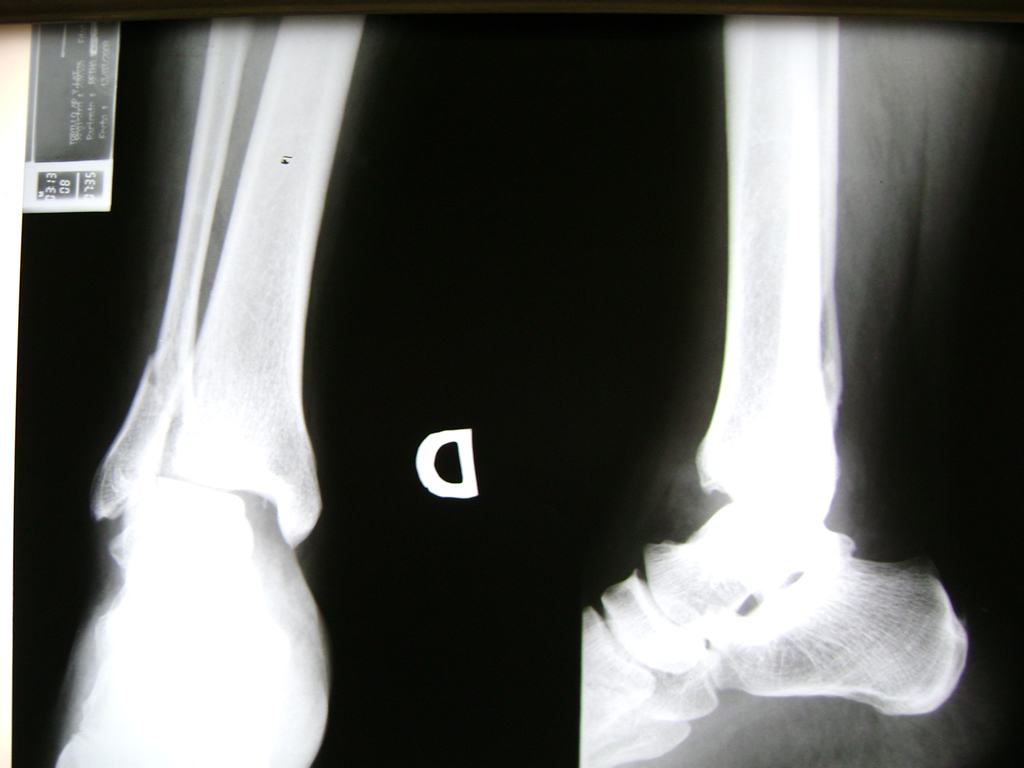

Una fractura de tobillo es la rotura de uno o más de los huesos del tobillo. Estas fracturas pueden ser:

- Parciales (el hueso está sólo parcialmente fisurado, no del todo).

- Completas (el hueso está perforado y está en 2 partes).

- Los extremos de los huesos están desalineados entre sí (desplazados).

- La fractura se extiende hasta la articulación del tobillo (fractura intra-articular).